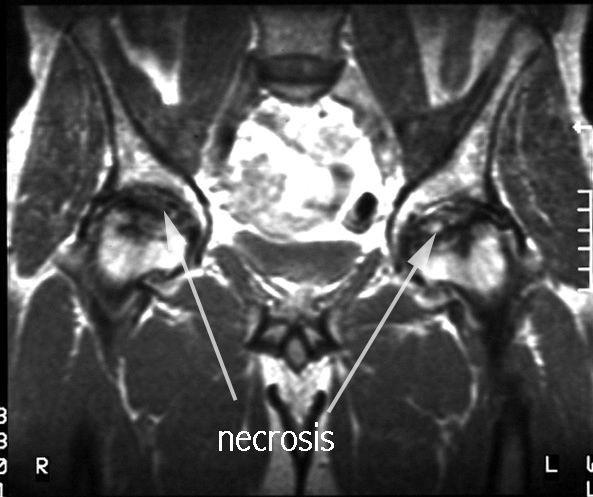

RESONANCIA MAGNETICA  muy sensible a los cambios isquémicos tanto en zonas epifisarias como en zonas metafisodiafisarias.  diagnóstico precoz: 2-5 días.  El patrón de imagen puede variar según el grado de afectación y la respuesta individual.  Una doble linea entre el hueso isquemico y no isquemico.  correlación entre las imágenes de RMN y los hallazgos histopatológicos  Visualiza la integridad del cartílago articular y permite identificar cuerpos libres intraarticulares.

RESONANCIA MAGNETICA